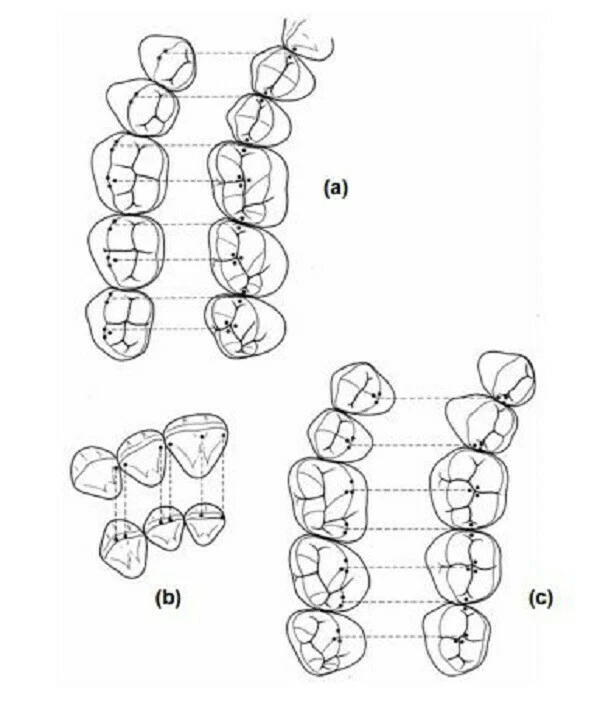

Hình bên dưới minh họa cho trường hợp sửa soạn bằng trâm K làm bằng thép không rỉ. Hình nảnh ống tủy bị dịch chuyển. Chú ý phần màu hồng là phần mô không được loại bỏ đầy đủ.

Trong hình bên dưới có thể thấy: trâm số nhỏ có thể uốn cong theo hình dạng ban đầu của ống tủy, sau khi nong rộng ống tủy với trâm số lớn hơn thì ống tủy có nguy cơ bị dịch chuyển.